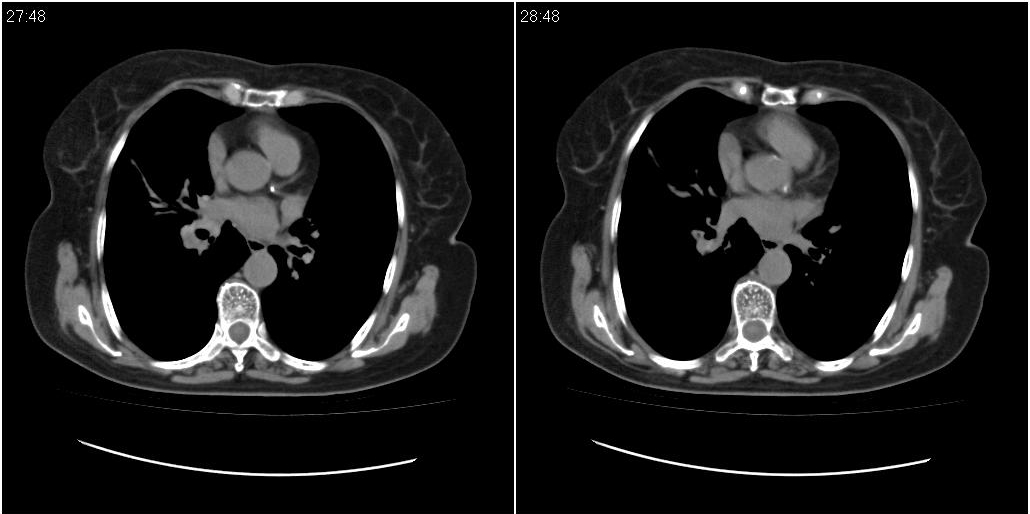

女性,72岁。去年9月份发现肺部病变,诊为肺结核并进行正规治疗至今,但复查后发现ct表现几乎没有变化。

右侧中叶支气管明显狭窄,建议行纤支镜检查!

右中间段支气管局限性狭窄,右中叶支气管亦稍显狭窄,但并未见明显占位表现,半年多了,无变化也许是好事,可能为炎性狭窄,建议继续随访。

右中叶炎性改变,支气管狭窄但较光滑,占位可能性不大。

右肺中叶节段性肺不张,考虑结核或慢性炎症,建议做纤支镜检查。